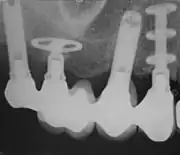

De moderne implantaten hebben meestal een schroefvorm, die in het bot wordt geschroefd. Deze schroef zal na verloop van tijd vastgroeien in het bot door een proces dat osseointegratie heet. Nadat het implantaat is vastgegroeid in het bot kan er een vervanging gemaakt worden voor de verloren tanden.

Grofweg kan de indicatie verdeeld worden tussen vervanging van een tand, vervanging van meerdere tanden en vervanging van alle tanden.

- Bij vervanging van een enkele tand zal er op het implantaat een kroon gemaakt worden.

- Bij vervanging van meerdere tanden zal er meestal een brug gemaakt worden maar het implantaat kan ook dienen als ondersteuning van een uitneembare constructie zoals een frameprothese.

- Bij vervanging van alle tanden in een kaak kan de opbouw bestaan uit een vaste brug of een uitneembare prothese welke verankerd wordt op de implantaten door middel van bijvoorbeeld drukknoppen of een staaf-huls constructie.